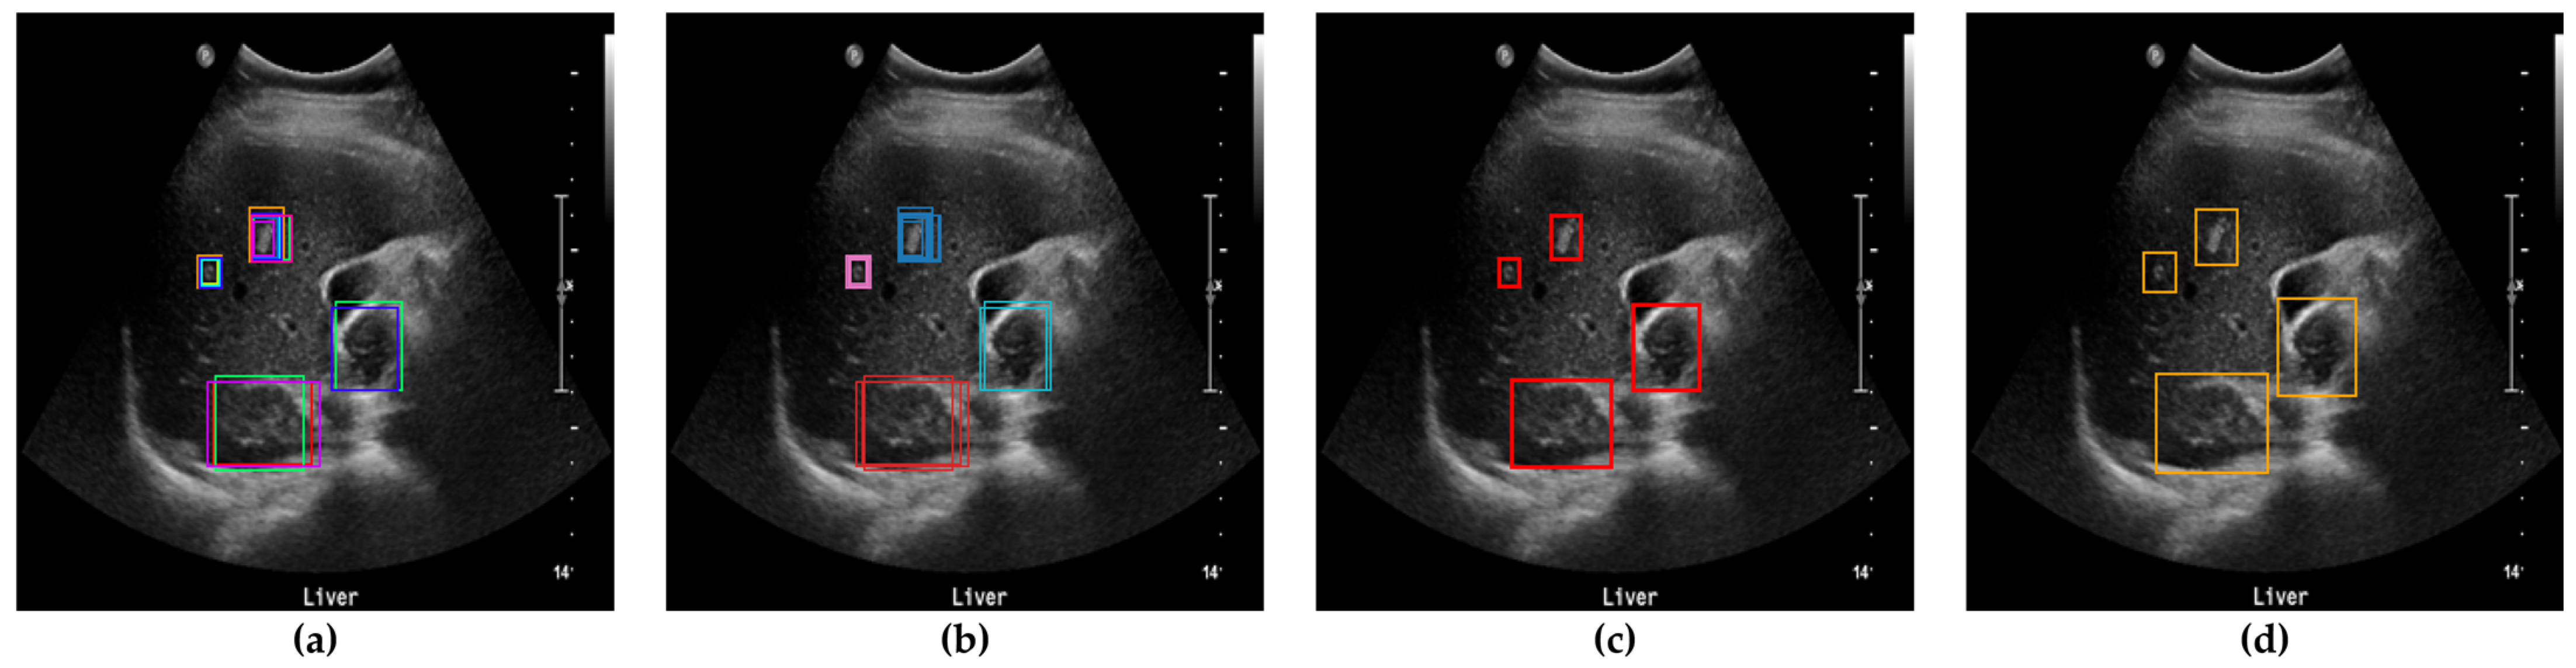

Figure 5.

Determination of bounding boxes using clustering, SM-WBF, and padding. (a) All bounding boxes detected by the ten networks. (b) Clustering of bounding boxes into four regions using DBSCAN. (c) Application of SM-WBF with SoftMax weights to the clustered regions. (d) Addition of padding to the bounding boxes in (c).

After clustering and outlier reduction, SM-WBF was applied to generate a single representative bounding box for each cluster. SM-WBF calculated weights for each bounding box by normalizing the mAP@0.5 values of the ten networks using the SoftMax function. These SoftMax weights were then used to combine the center coordinates and dimensions of the bounding boxes within each cluster through a weighted average approach. This method ensured that bounding boxes from higher-performing networks contributed more significantly to the result. Details of this process are illustrated in Figure 7.

Figure 7.

(a) An image with all bounding boxes detected by YOLOv8 overlaid, and the results of bounding box optimization through (b) clustering, (c) SM-WBF, and (d) padding. (e) Ground truth bounding box.